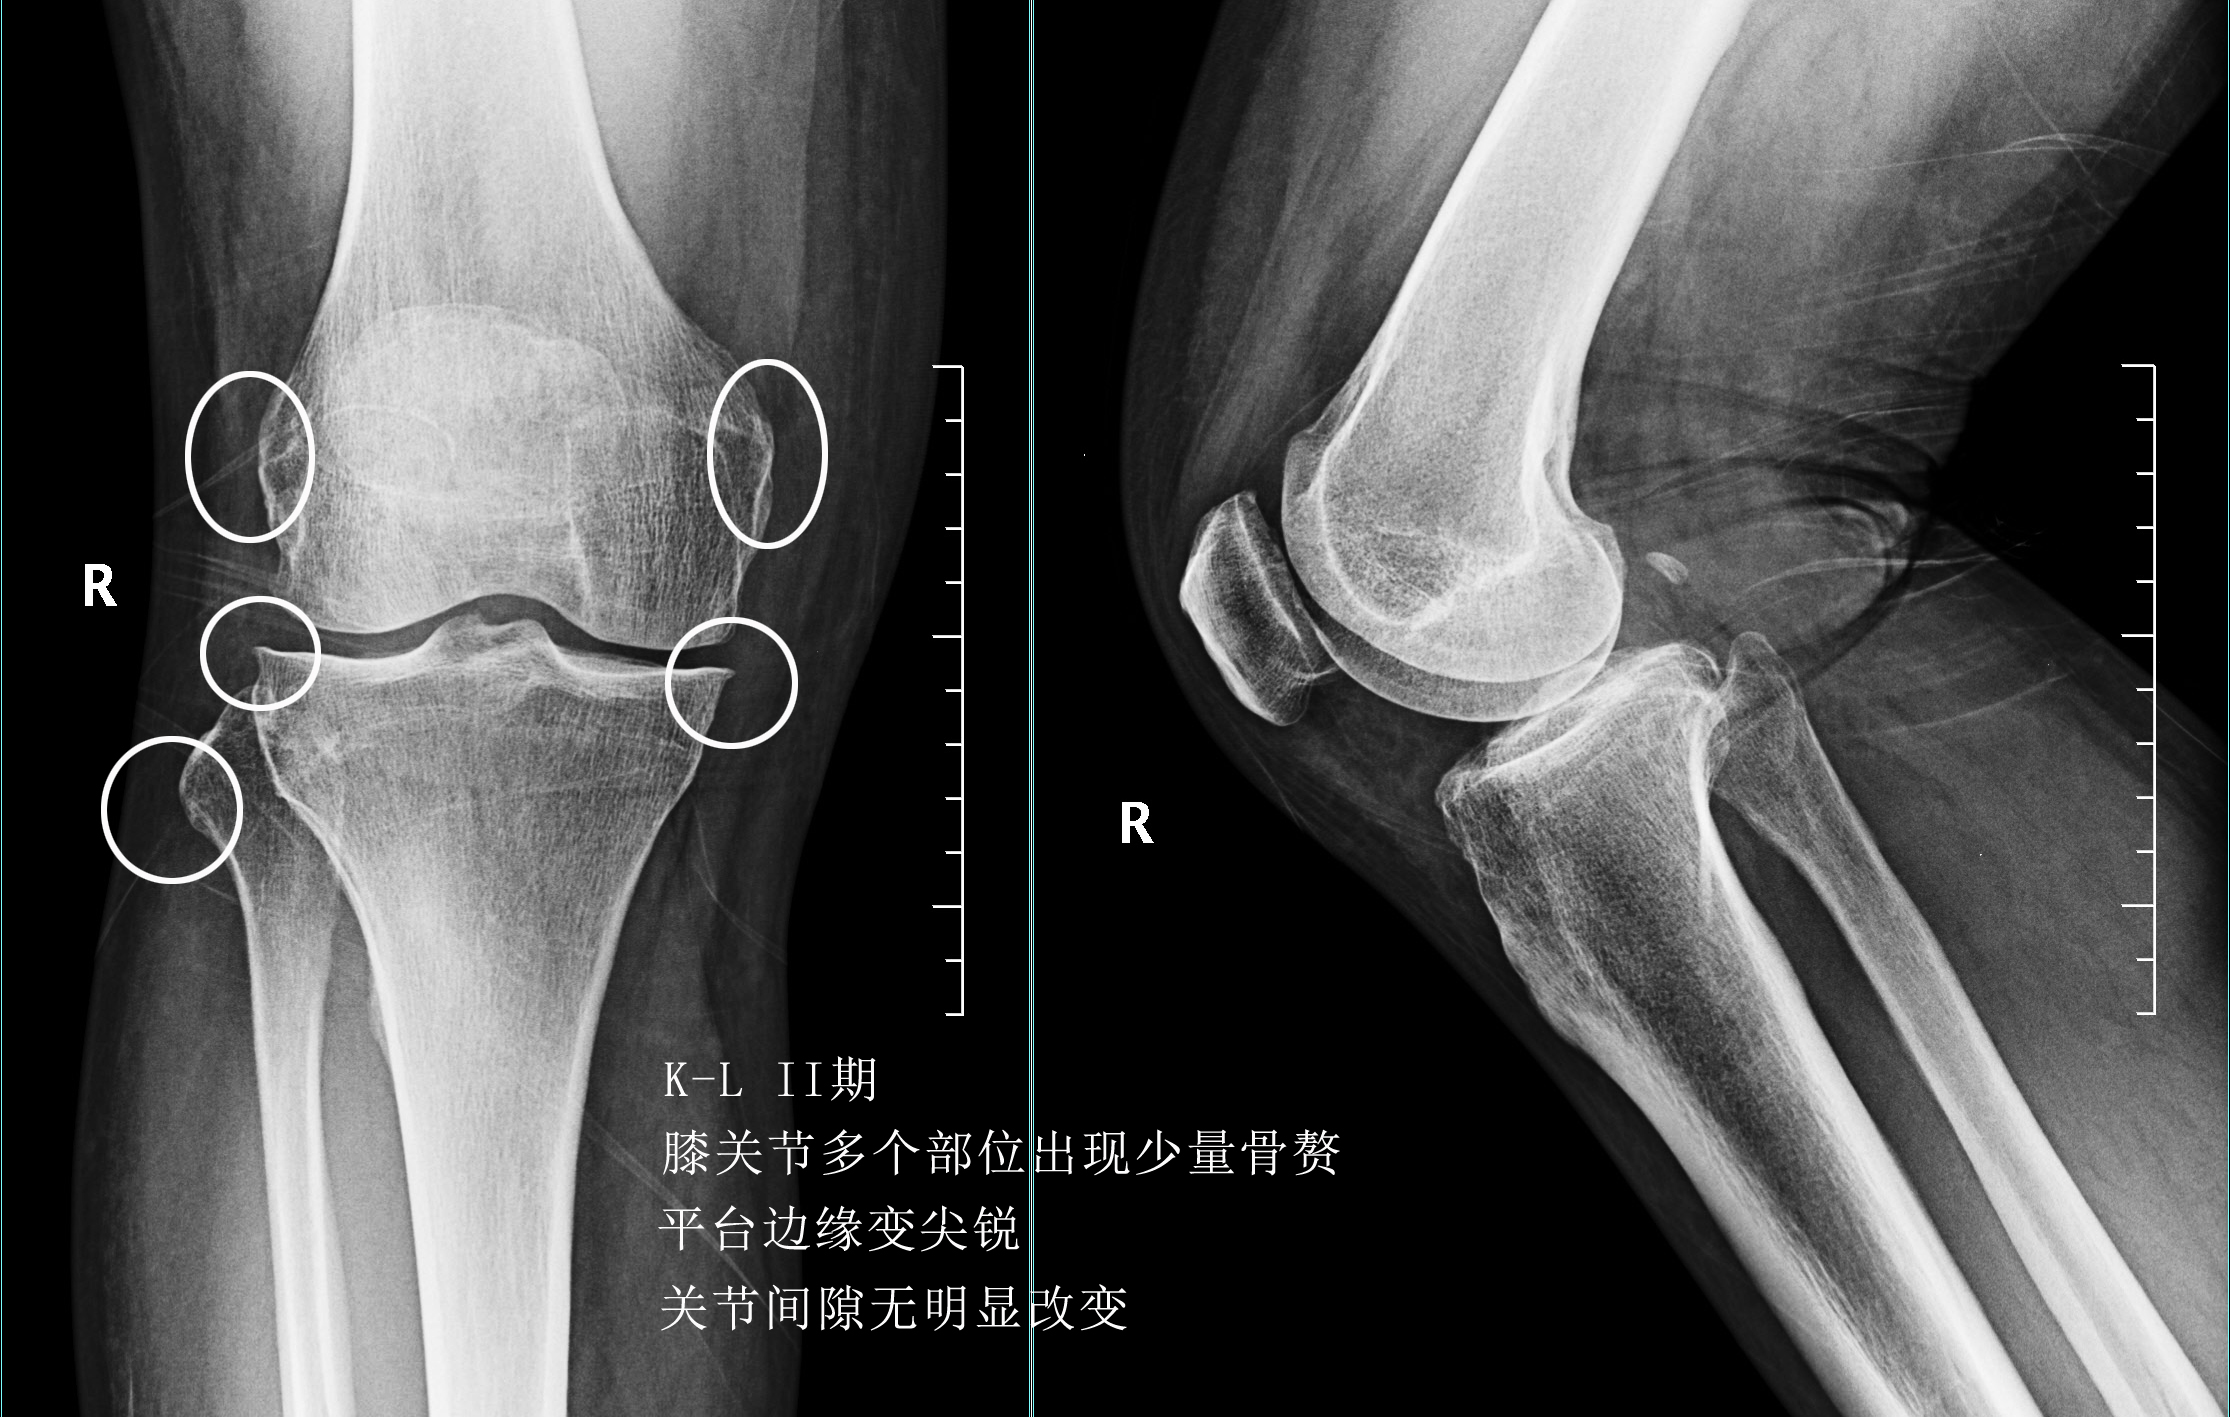

前面已经说到骨关节炎会导致骨赘的形成以及关节间隙的狭窄,所以我们依靠膝关节x片子来初步判断骨关节炎的病情,通常我们采用K_L分期判断病情。

0期的患者:也就是正常的患者,患者不会有任何的症状。

一期患者:患者的关节会开始有轻度的无罪行程,一般这个阶段的患者会有比较明显的上下楼梯的疼痛或者是不适,但是往往走平路反而正常,所以很多这个阶段的患者并没有得到很好的重视。在这个阶段,如果能开始注意保护我们的关节,减轻体重、减少对于关节的使用往往是可以逆转的,但是正是由于症状不是特别的明显,反而很多人忽视了这个病情。

二期患者:2期的患者关节的那个骨赘就已经开始明显增多了,但是这个时期关节的间隙仍然不会发生狭窄,这就说明关节内的软骨虽然已经有了磨损,但是磨损的程度还可以,不是特别的重。

往往这个时期的患者,如果症状比较明显,在医院检查发现了骨关节炎,治疗起来反而效果最好。因为关节的软骨还没有磨损的特别严重,此时我们通常可以采取给于关节内进行玻璃酸钠、几丁糖或者是富血小板血浆因子注射的办法来减缓软骨磨损的进程,缓解患者的症状。此时也可以给予患者口服氨糖。

三期患者:3期的患者不仅有了骨赘大量形成,而且关节间隙已经开始发生了明显的狭窄,患者的症状会越来越严重,很多会表现出来蹲起的疼痛,甚至有的患者不能长时间的行走,否则次日关节就会有明显的肿胀,有的患者在屈伸关节的过程当中会听到响声,类似于冬天我们用脚踩雪的那种响声。

在此阶段我们通常仍然会采取关节内注射的办法以及一些保守治疗的办法,缓解患者的痛苦。患者也可以口服仙灵骨葆这一类的中成药。

四期患者:4期的骨关节炎患者关节已经出现了严重的畸形,这个时期患者会非常的痛苦,关节会有严重的畸形,通常不能行走很长的距离,有一些患者甚至行走500米就疼痛难忍了。而且患者通常会出现比较明显的休息痛以及静息痛,什么意思呢?就是说,不动也痛。

此时我们只有通过进行关节置换手术的办法,才能帮助患者来解决痛苦。医生也知道很多患者不想做全膝关节置换术,所以说现在也研究出来单髁的置换手术,也算是一种保膝治疗。